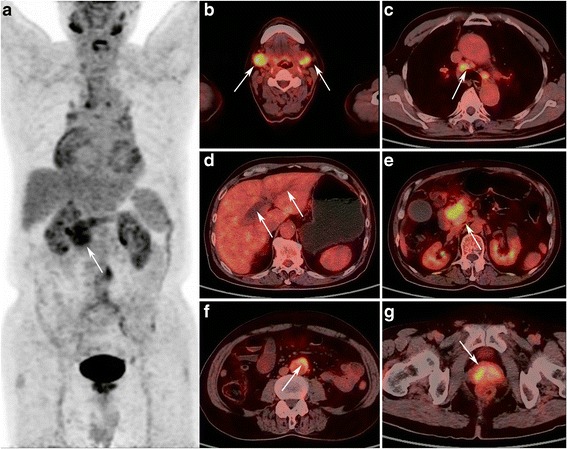

Fig. 2.

A 66-years old male patient with focal AIP in the pancreatic head. MIP PET (a) and PET/CT fusion (e) images shows localized enlargement of the pancreatic head with increased FDG uptake (arrow), with early and delayed SUVmax of 6.7 and 8.0, respectively. PET/CT fusion images shows (b) increased FDG uptake in bilateral submandibular gland, with a SUVmax of 7.9; (c), enlargement of mediastinal lymph node with increased FDG uptake (SUVmax, 5.7); (d), dilatation of bile duct; (f), retroperitoneal fibrosis around artery; (g) inverted “V” shaped high FDG uptake in the prostate

Fig. 3.

A 59-years old male patient with pancreatic cancer. MIP PET (a) and PET/CT fusion (e) images show a mass in the pancreatic head with increased FDG uptake (arrow), with early and delayed SUVmax of 9.3 and 10.8, respectively. Compared with AIP patients in Fig. 2, no increased FDG uptake foci in the salivary gland b), mediastinal lymph nodes (c), retroperitoneal space (f), and prostate (g) are observed, as well as no bile duct expansion (d)